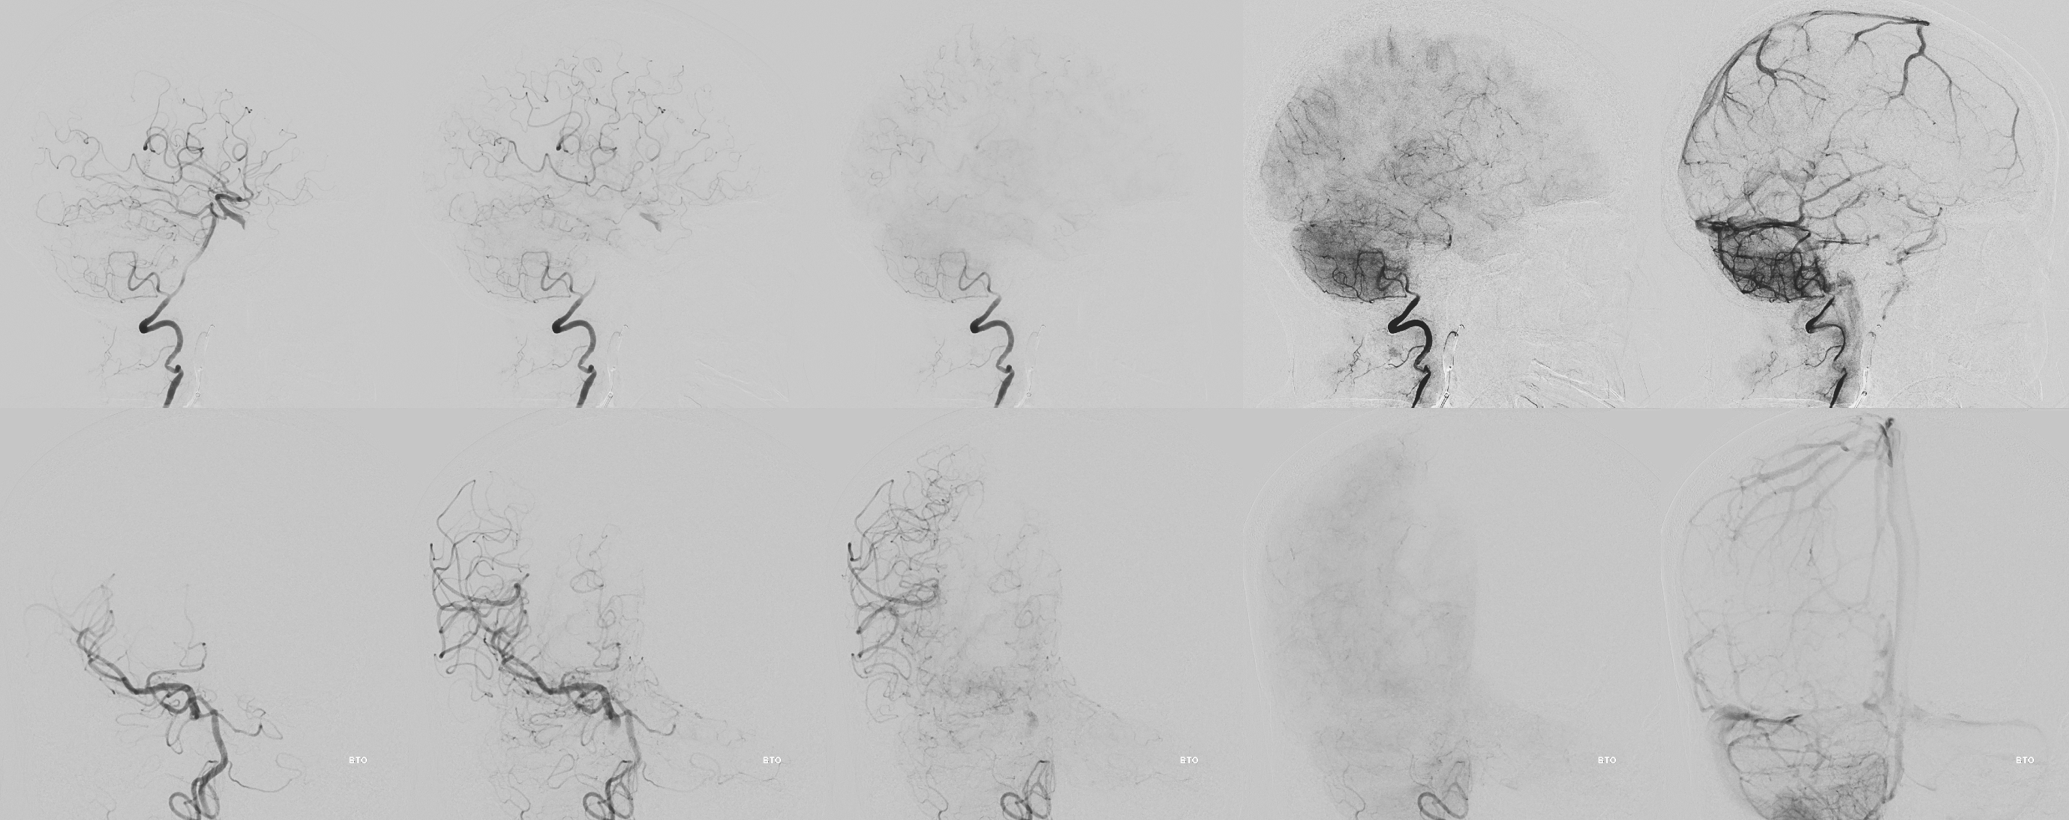

Angio — barely any inflow at the base. Vasa vasorum are basically impossible to see on 2D-DSA. Cone Beam CT is needed

BTO. The A1 is hypoplastic

Cone Beam CT

With arrows — vasa vasorum are curiously dural in origin here — via deep recurrent meningeal (dashed arrows). Solid arrows are surface vasa vasorum

Sagittal MIPS show hazy eggshell wall enhancement